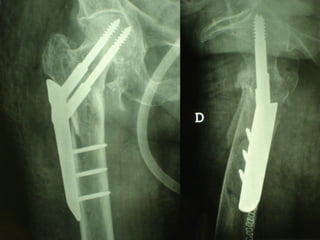

The GOTFRIED plate

La placca a compressione percutanea (PC.C.P.) di Gotfried è un mezzo di sintesi studiato per assicurare un “impattamento controllato” delle fratture pertrocanteriche grazie alle due viti telescopiche prossimali che garantiscono una ottima stabilità rotazionale

Con la placca di Gotfried non si è mai riscontrato un danno iatrogeno del muro laterale e nessun collasso della frattura.Ciò è dovuto al fatto che i fori per l’applicazione delle due viti prossimali sono di piccolo diametro (9 mm) rispetto ai 16-32 mm necessari per introdurre la vite cefalica di un chiodo endomidollare o di una vite-placca a compressione.

La placca PC.C.P. viene inoltre applicata per via percutanea attraverso due piccole incisioni ottenendo in tal modo un minimo trauma chirurgico ed una  perdita di sangue estremamente ridotta in pazienti che per l’età  sono già in condizioni  critiche

Dal Gennaio 2005 ad Agosto 2006 110  placche di Gotfried Età media  : 78 anni (range 29-94) Tempo chirurgico: 30 minuti (range 12-45) IMMEDIATA CONCESSIONE DEL CARICO